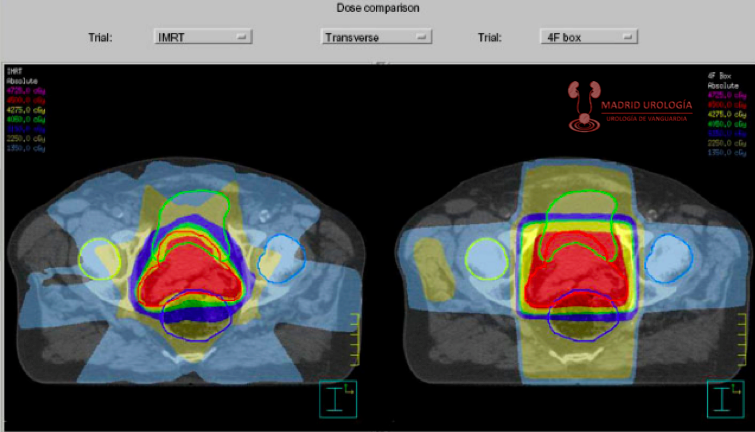

RADIOTERAPIA PREQUIRURGICA

Teóricamente la administración de radioterapia preoperatoria permitiría tener células tumorales menos viables durante la manipulación quirúrgica posibilitando la reducción de márgenes quirúrgicos con la posible disminución de la recidiva local.